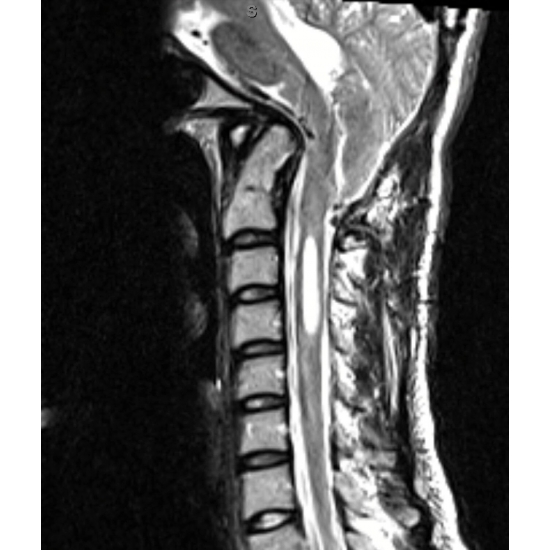

MRI cervical spine without contrast: Chiari 1.5 malformation with extensive syringomyelia of the cervical cord and partially imaged hydrocephalus of the fourth ventricle. Disc preserved in height and signal with no herniation or osteophyte complex C2-T1. Case Photo #5

MRI cervical spine without contrast, post-operative day 1: associated hydromyelia of spinal cord; partially visualized 4th ventricle. Case Photo #8

MRI cervical spine without contrast, 3-months post operative: 20 mm caudal displacement of cerebellar tonsils, C2-C7 syrinx. Case Photo #9

MRI cervical spine without contrast, 9-months post operative: stable syrinx and displacement. Case Photo #10